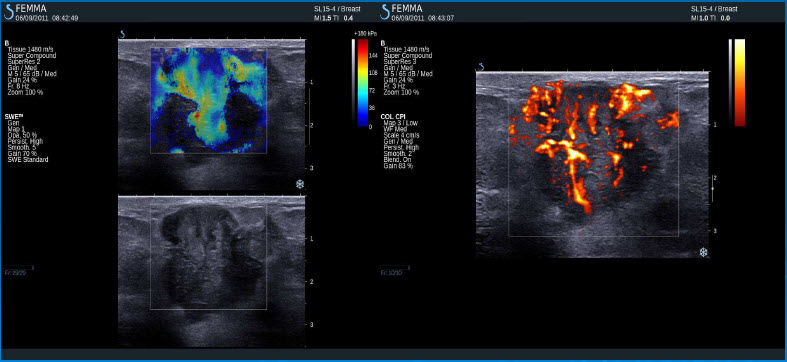

Invazivní duktální adenokarcinom

Inflamatorní karcinom

Invazivní lobulární karcinom

Invazivní duktální karcinom